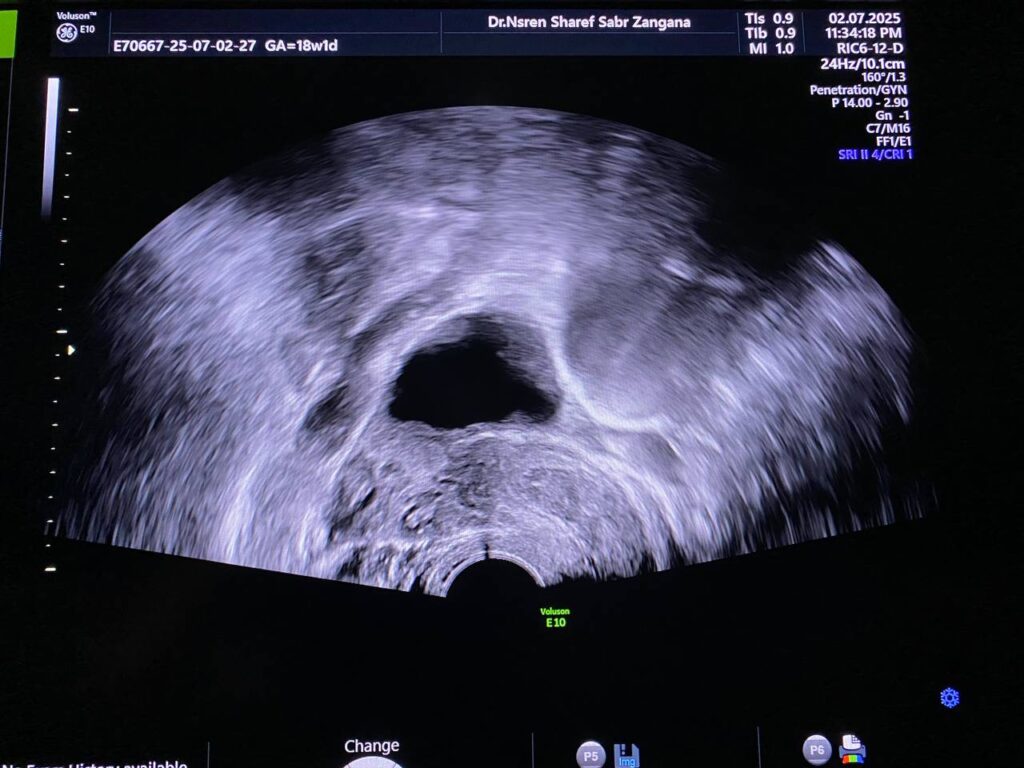

Bulky size, R/V uterus, endometrial lining thickness 13mm, with presence of isoechoic mass 36x12mm , within the cavity and nearly at level of interval os , incomplete abortion ? submucosal fibroid ? please for further study ill-defined endo-myometrial junctional zone, hypertrophy & asymmetry of the junctional myometrial layer, with presence few small cystic within the junctional layer, picture mostly of adenomyosis changes

· Right ovary contain avascular circumscribed cystic mass 38x38mm , mostly physiological, for follow up

· Left ovary normal in size, no mature nor dominant follicle

· No adnexal mass

· No free pelvic fluid seen